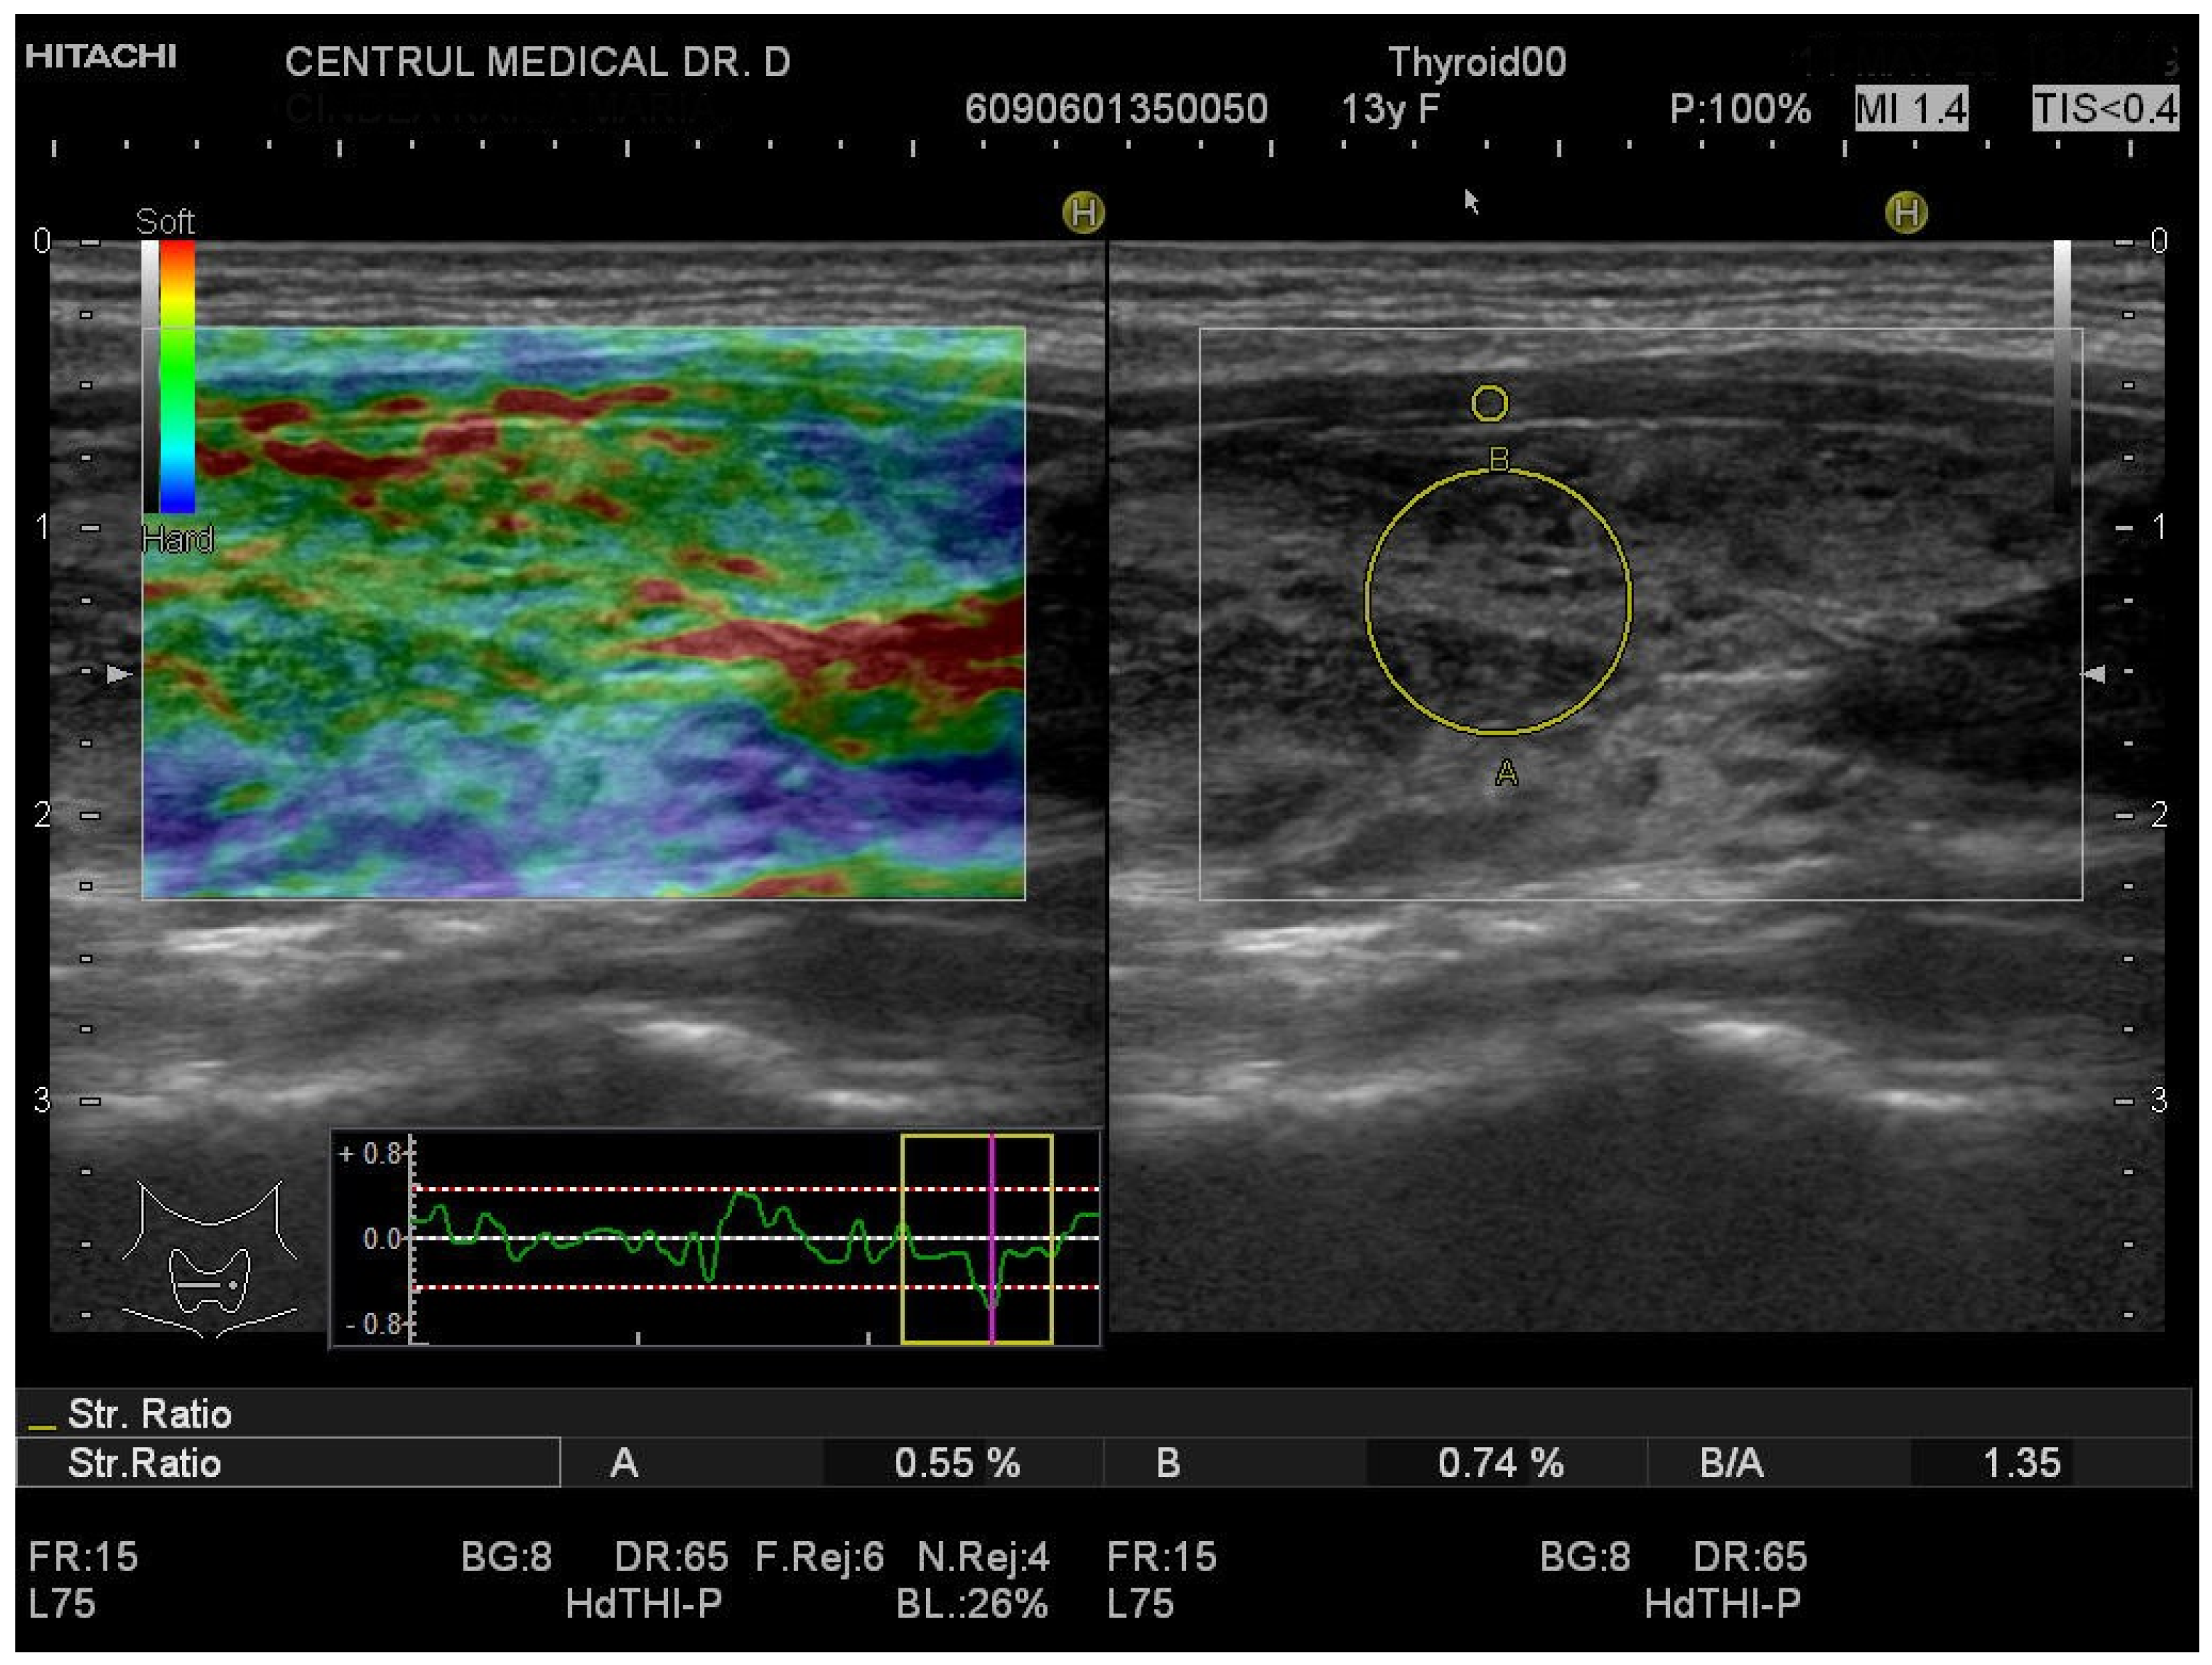

2.4. Conventional Ultrasound and Elastography Examination

3.1. Strain Elastography Measurements